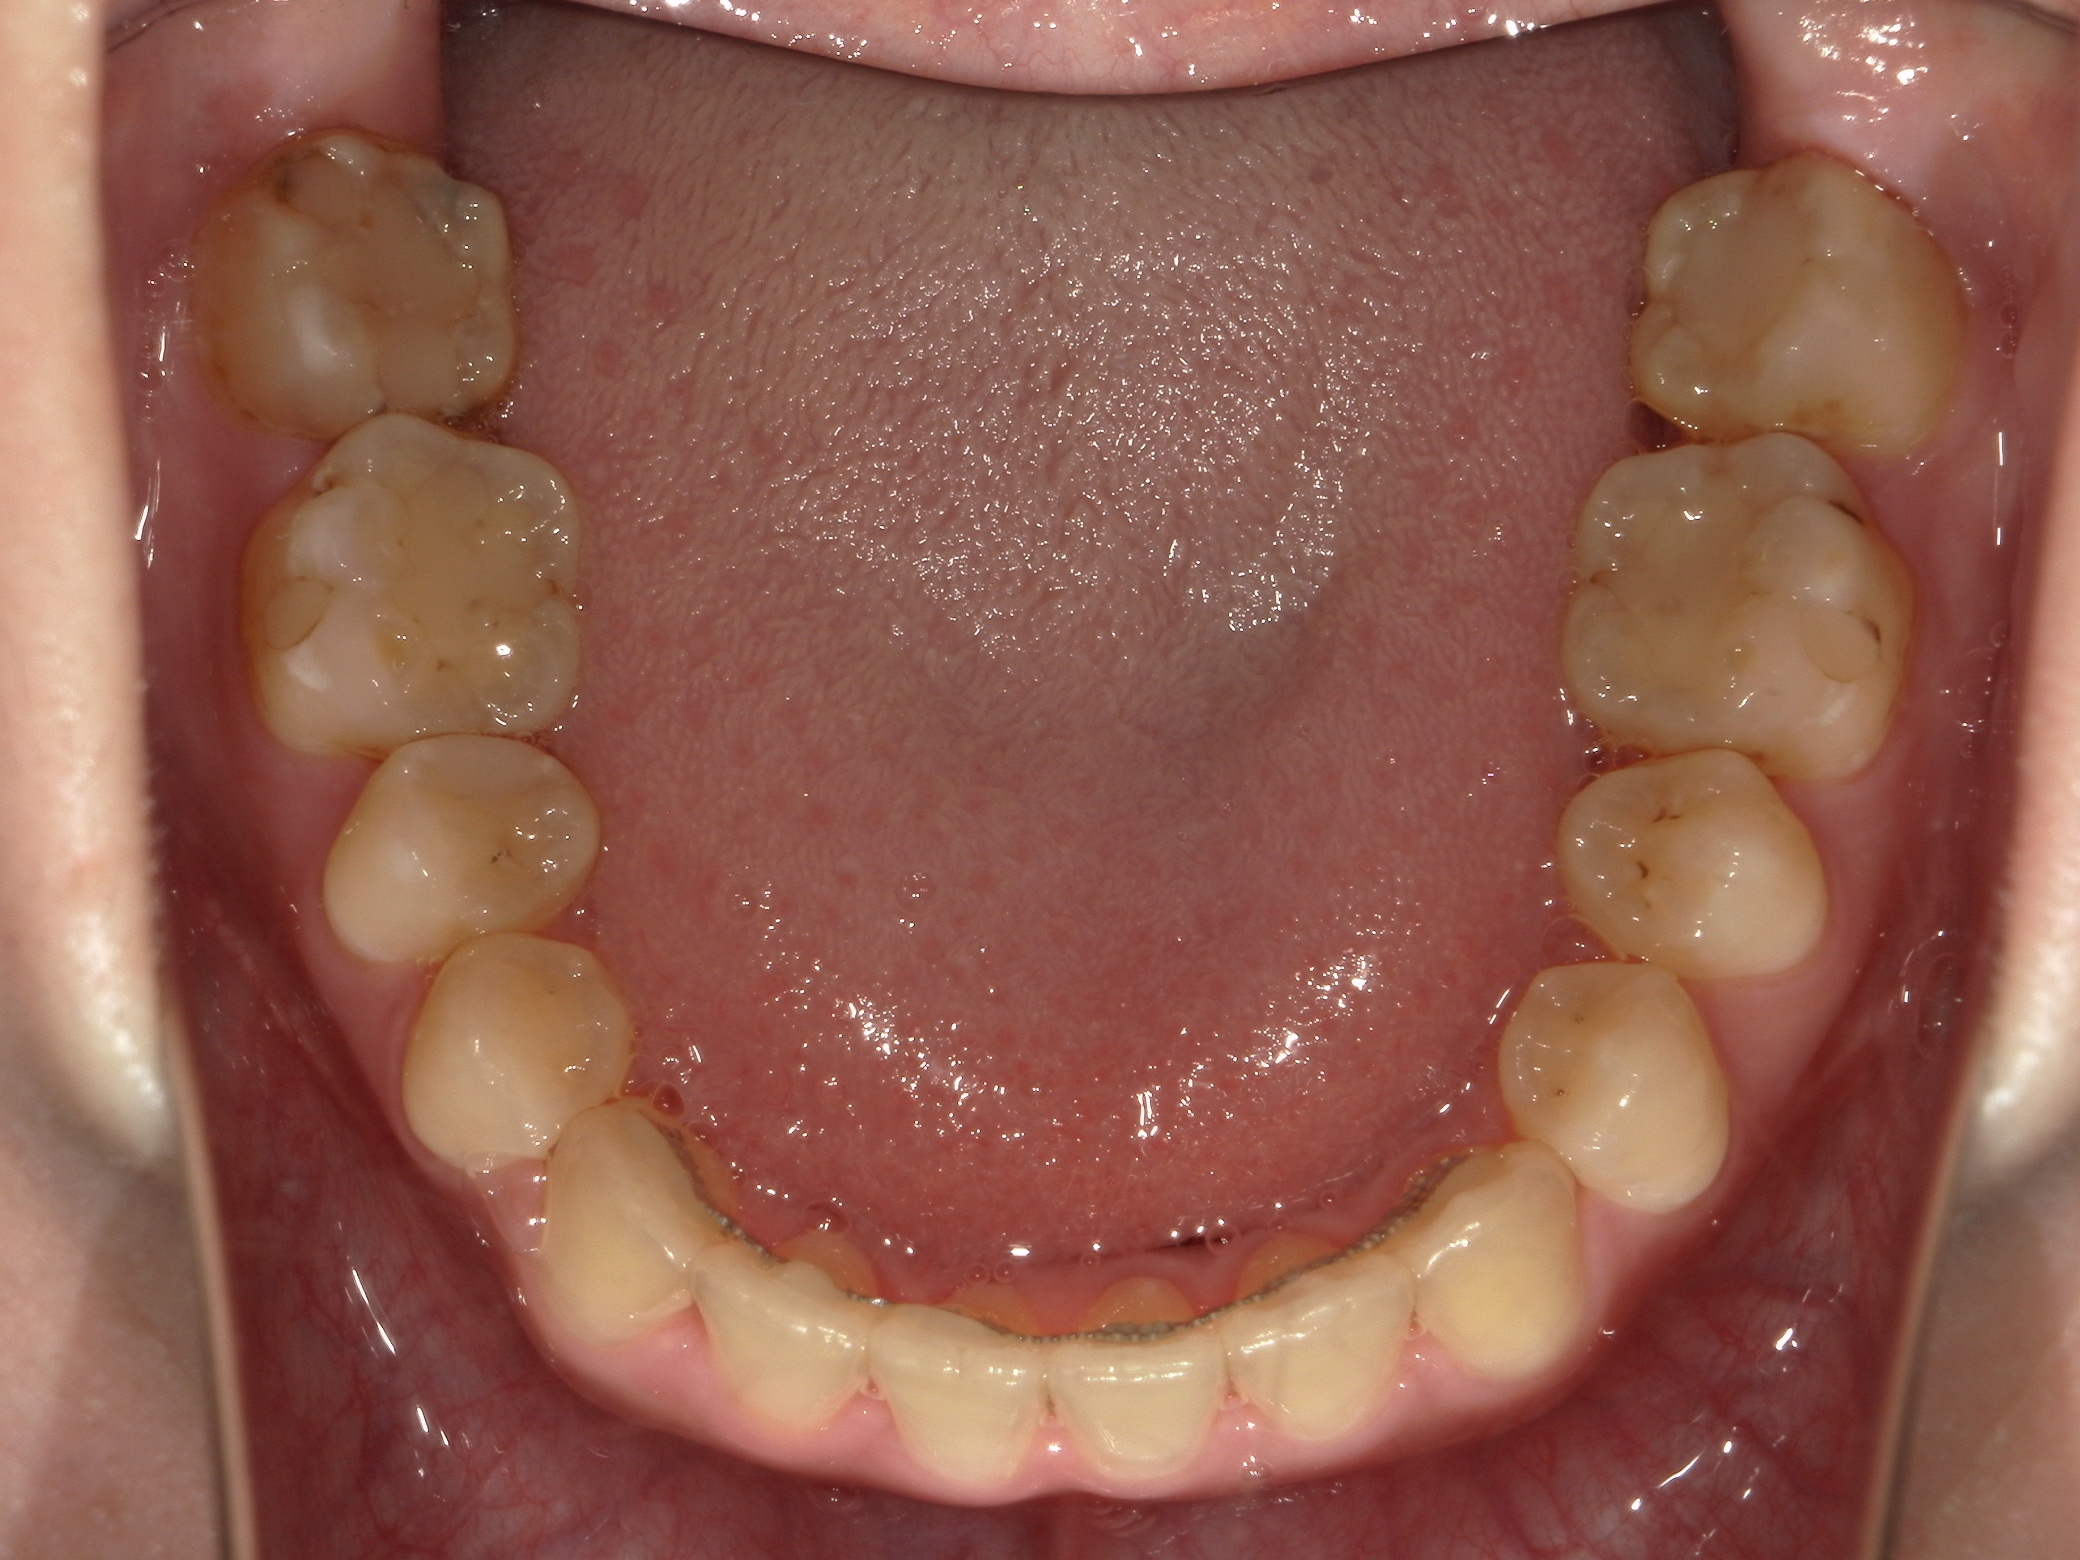

口内下

治療前

治療後

上下の歯列のがたつきは軽度でしたが、下あごの骨が前方に位置しており、上下の前歯が突き合わせの咬み合わせになっていました。

上下の歯を並べた後、上下のあごの骨を切って動かす手術を行い、骨格から改善を行いました。

結果、治療後の写真の通り正中は一致し、犬歯・臼歯ともに正しいポジションにて、美しい見た目と適切なかみ合わせを獲得できました。